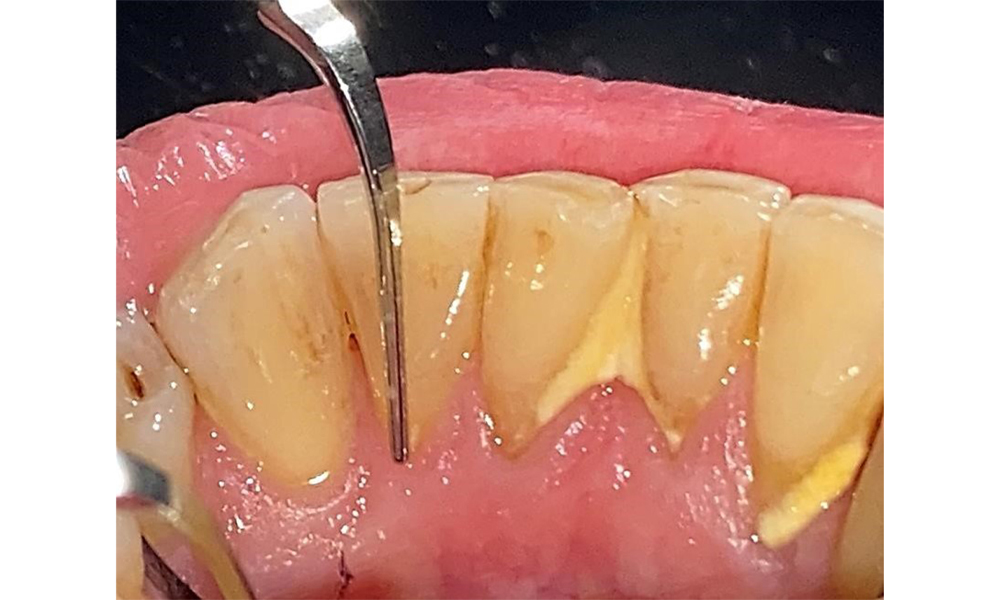

Probing to document the findings in tooth 27 mesiopalatal.

Fig. 8: Probing to document the findings in tooth 27 mesiopalatal. © Dr R. Krapf

The documentation of periodontal findings, including pocket depth probing and bleeding status, is mandatory during each dental appointment due to the presence of periodontitis (Fig. 8). This will record the individual therapeutic needs and facilitate a rapid response to any progression of the pre-existing periodontitis.

Detailed periodontal findings, including the documentation of pocket depths, bleeding on probing, recessions, furcation involvement and degree of loosening, must be examined annually.